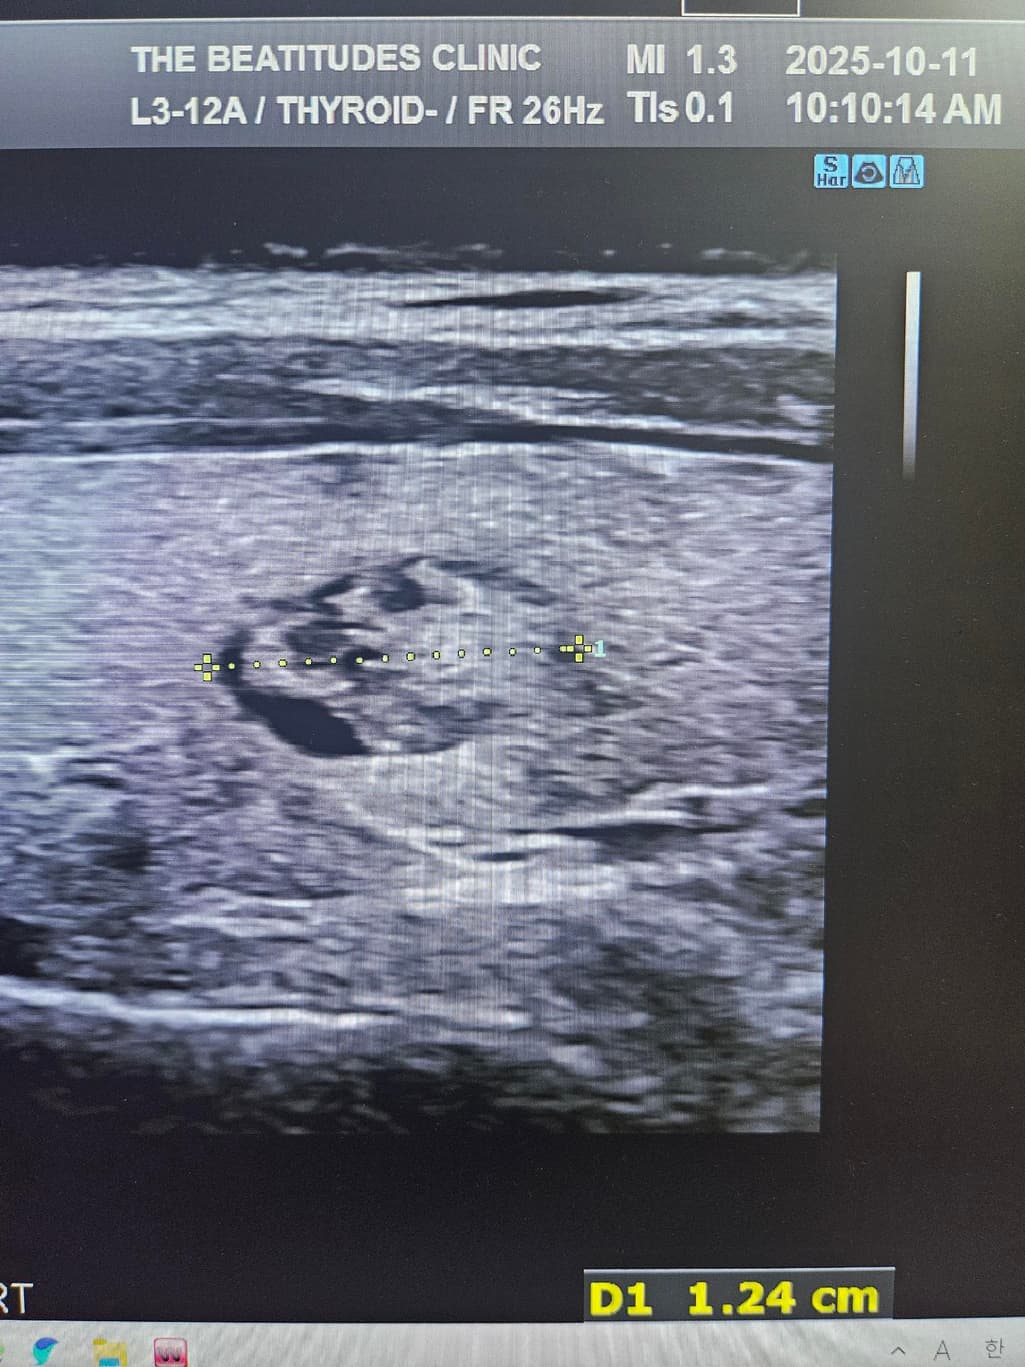

갑상선초음파하고 세침검사 권유받았는데 위의 세개의 사진은 같은 혹이 맞는건가요? 1개 있다고 얘기해줘서 봤는데 사이즈가 이렇게나와서 가로 세로 폭 값인건지 여쭤보고싶습니다

두번째 사진의 경우는 결절이 보이지 않으며 협부의 두께를 측정한 것 같습니다.

초음파에서 첫번째, 세번째 사진의 급성 연골 오른쪽에 위치한 오른쪽 갑상선에 동그란 혹이 관찰되며 사진으로는 사이즈를 정확하게 구하기 어렵지만 1.5 cm 이상으로 보이며 혹 안에 균질하지 않은 모습으로 악성 혹은 양성이라고 해도 정기적으로 관찰해야 하는 종양으로 보여 조직 검사를 받는 것은 필요한 것으로 보입니다. 갑상선 종양은 다른 종양에 비해 예후가 좋아 적절한 치료를 받으면 대부분 완치가 가능합니다